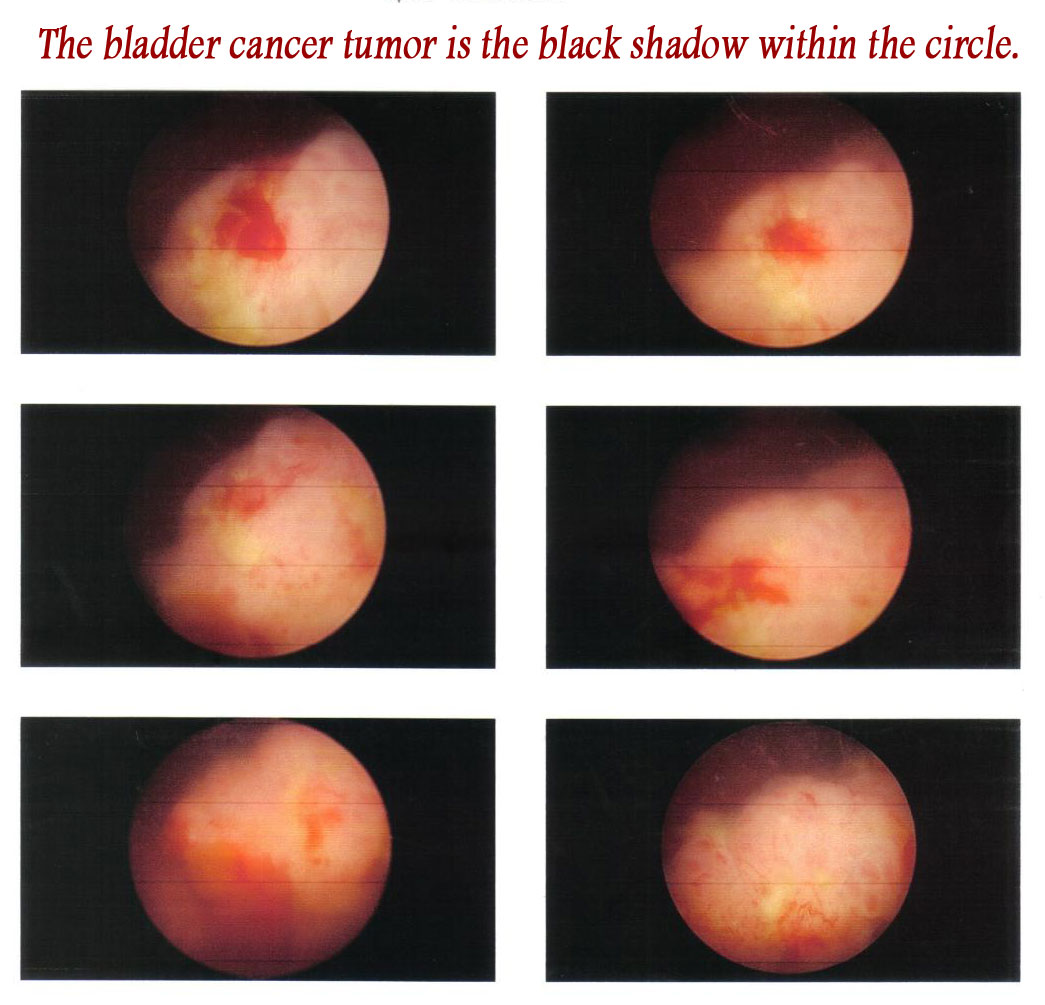

Cystoscopic image of polypoid urinary bladder tumor. Image courtesy of …

Cystoscopic findings in bladder tumors. (a) White light mode (left …

Enhanced Cystoscopy for Early Bladder Cancer – PeopleBeatingCancer

Blue Light Cystoscopy Increases Bladder Cancer Detection Rate – Renal …

Tumors of the Bladder: Cystoscopic and Radiographic Appearance